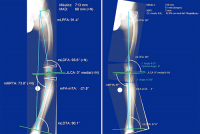

Mô-đun Long Leg của phần mềm MediCAD cho phép bác sĩ xem tổng thể và lập kế hoạch cho các ca nắn chỉnh xương hiệu quả, nhanh chóng.